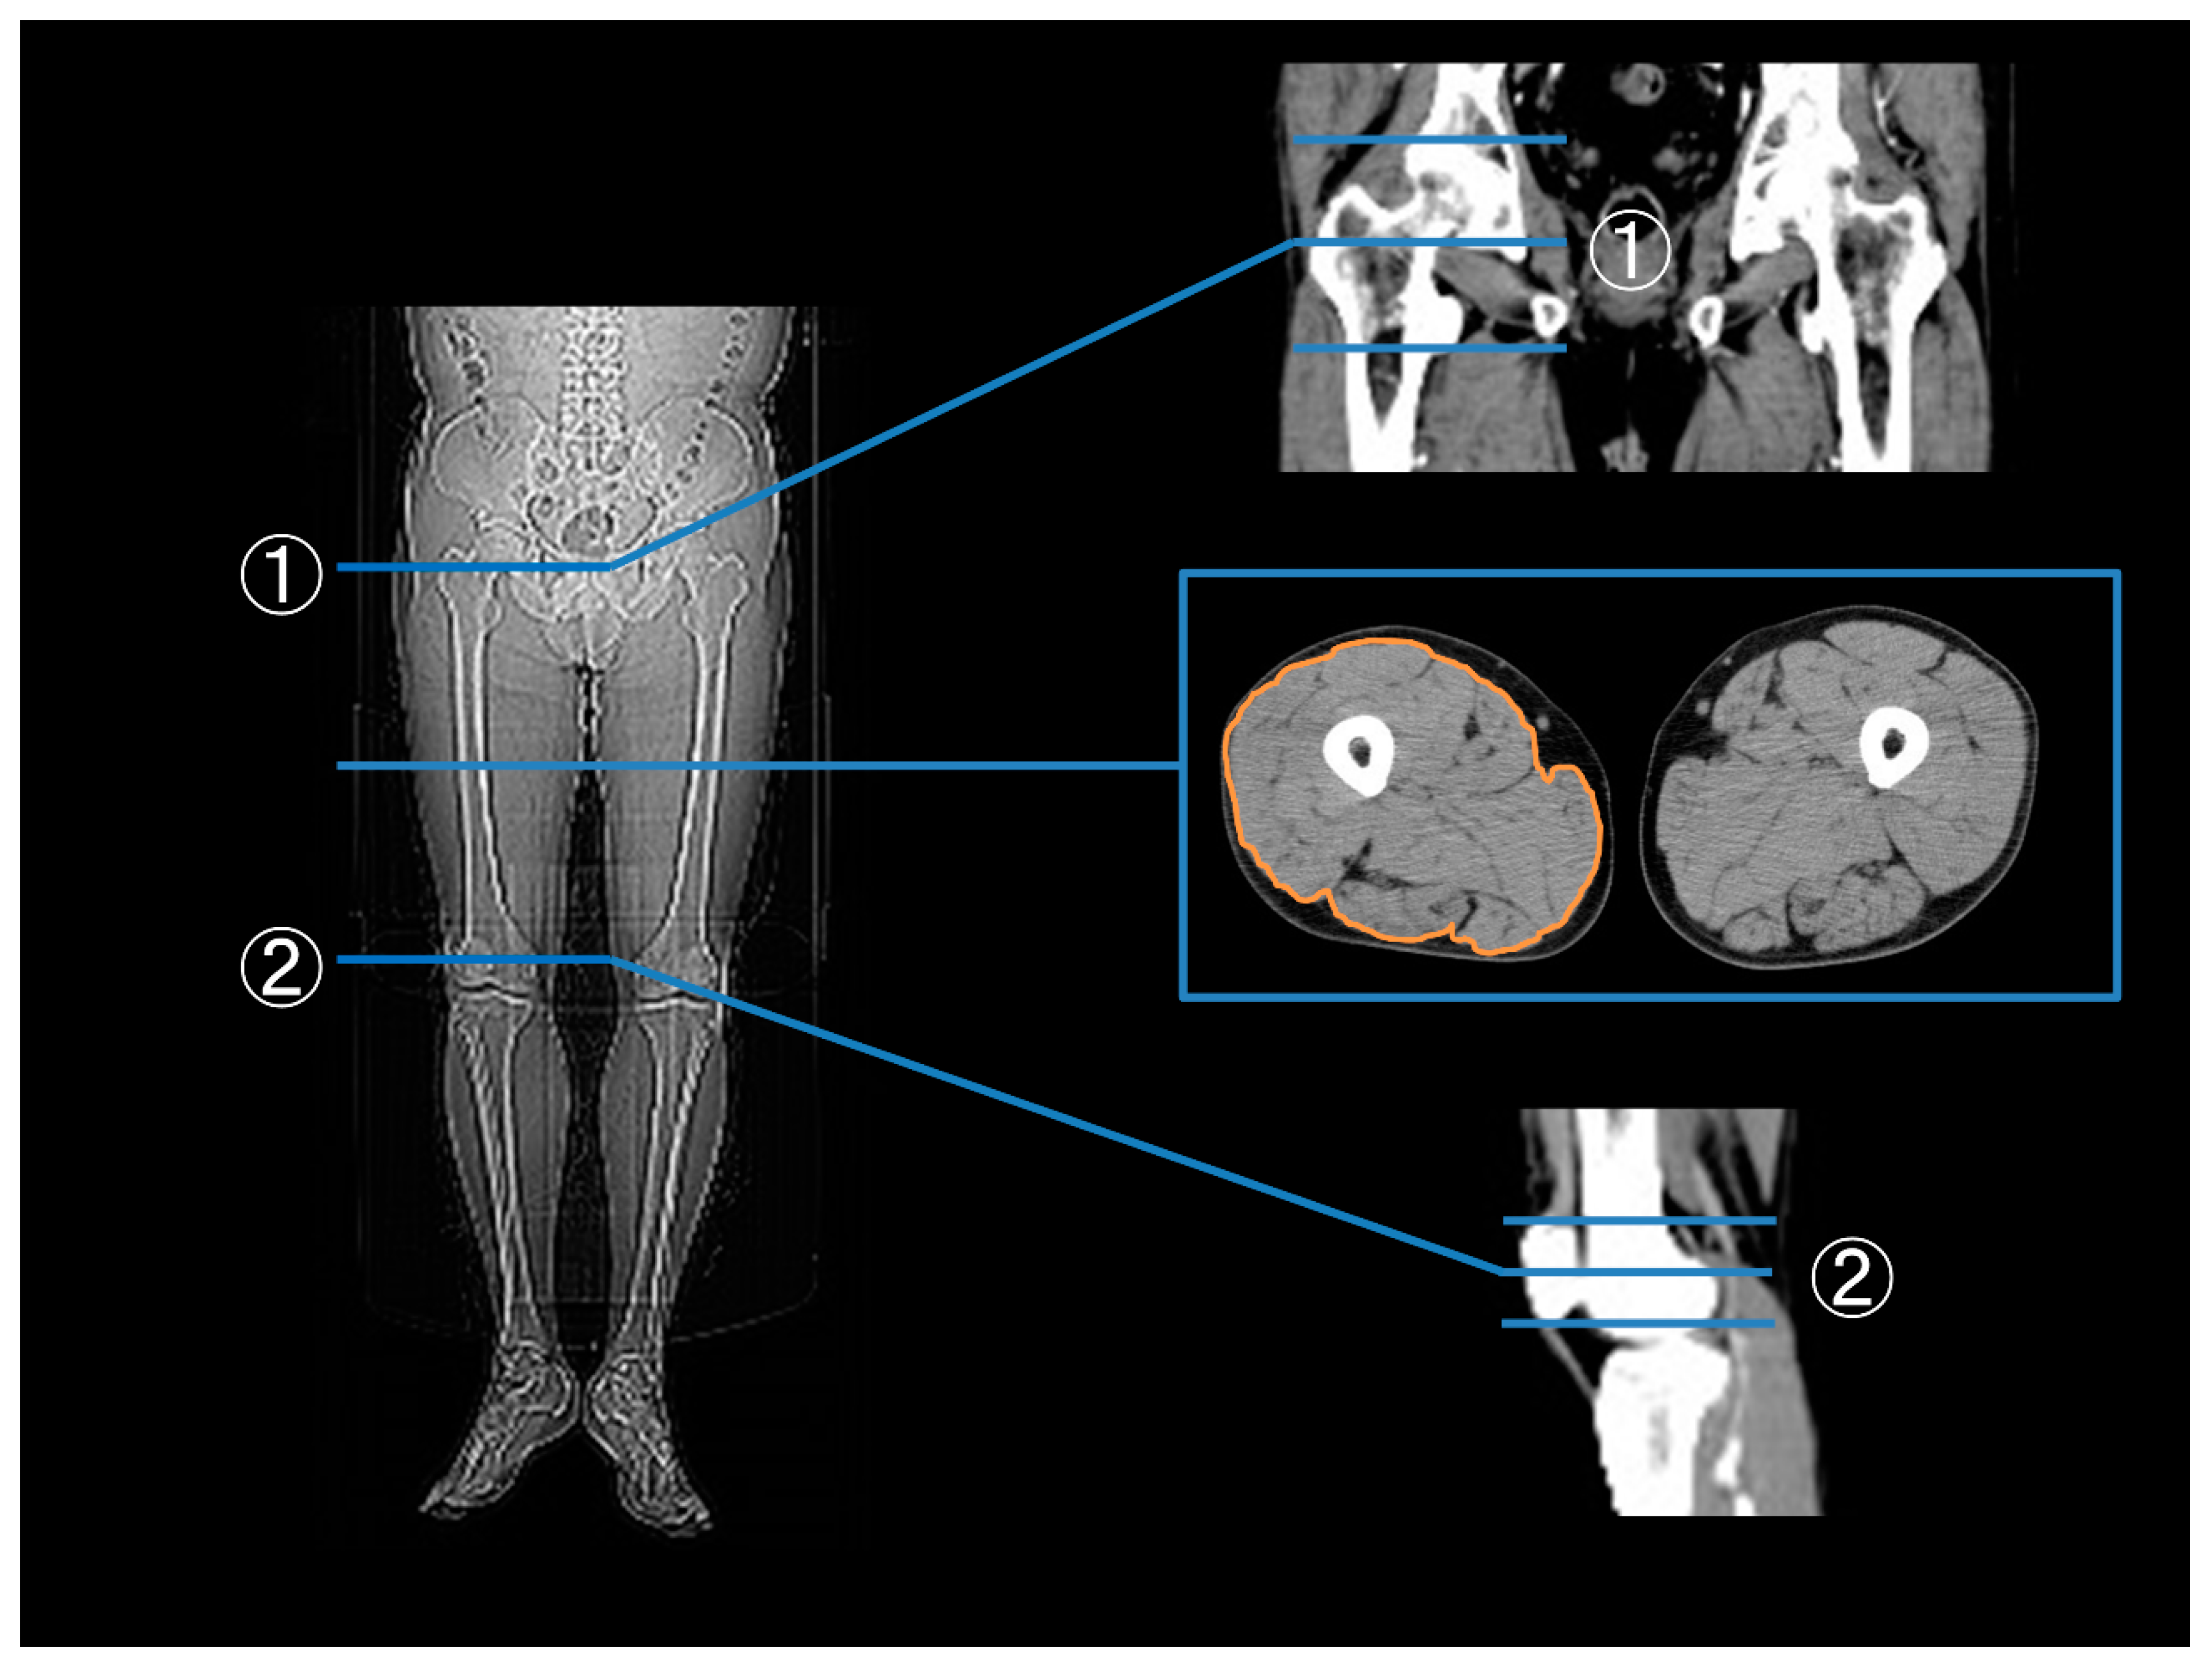

2.4. Measurements of the Thigh Muscle Area, Apo A1, B, OGTT, and Glycated HbA1c

3.1. Thigh Muscle Area before and after EVT